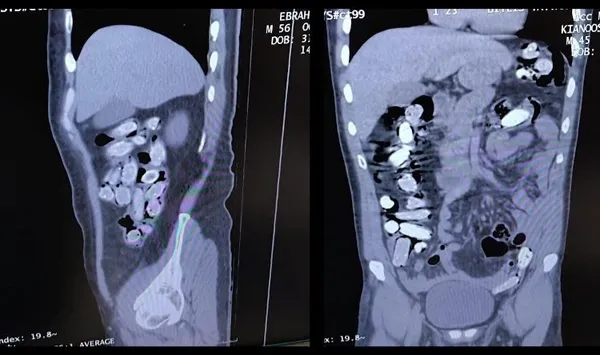

Emniyet Müdürlüğü'nde ifadeleri alınan şüpheliler daha sonra Bitlis-Tatvan Devlet Hastanesi'ne götürülerek röntgen ve tomografileri çekildi. Şüphelilerin mide ve bağırsaklarında çok sayıda yabancı cisim taşıdıkları tespit edildi. 1 kilo 340 gram Afyon Sakızı yapılan tıbbi müdahaleyle çıkarıldı. İşlemlerinin ardından adliyeye sevk edilen 2 şüpheli, çıkarıldıkları mahkemede tutuklandı.